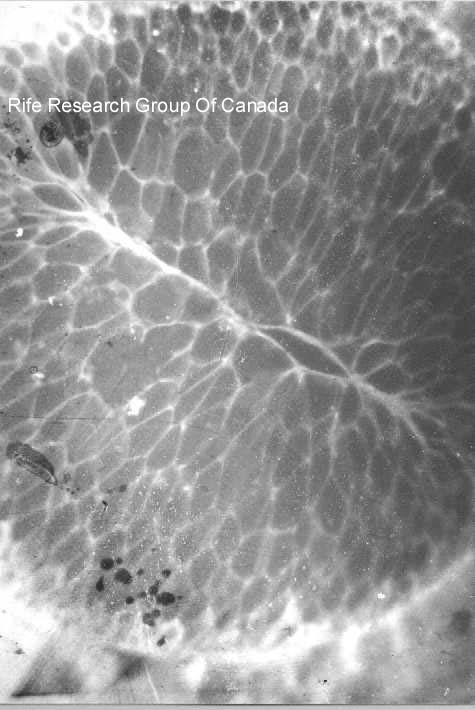

Ameba 5000x Histolitica

Typhoid Bacteria with Rife Stain

Enlarged to 300,000x

E. Coli with Rife Stain 6000x

Tuberculosis in rod Form

Strombilitis Intestinalis

T.B. Kidney - Rods in Cells, 2000x AgNO3 Stain

Tetanus